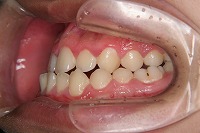

右

反対咬合と下顎が出ている事を主訴に来院された、初診時18歳1か月の男性です。診断「上顎骨の後方位による骨格性反対咬合」非抜歯での矯正治療と、下顎を後退させる外科手術を併用して治療を行いました。